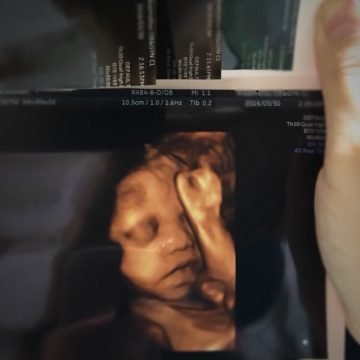

妊婦健診中に通常3回とされる血液検査ですが、私、妊娠20週のときを除くすべての健診で血液検査を行いました。なぜなら、貧血が全然治らなかったからです。妊娠中に貧血になった私の食生活や、今だから思う注意したいことなど体験を通してお伝えします。

広島の自治体発行の母子手帳を手にしてから初めての妊婦健診(妊婦健康診査)は8週のときでした。初めての妊娠だったので、健診のときにどんなことをするのかなんて知識は皆無。看護師さん、医師に言われるまま検査等を行いました。その流れのなか、行った血液検査。結果が出ると、医師からは「貧血だから注意してね」と念を押されました。